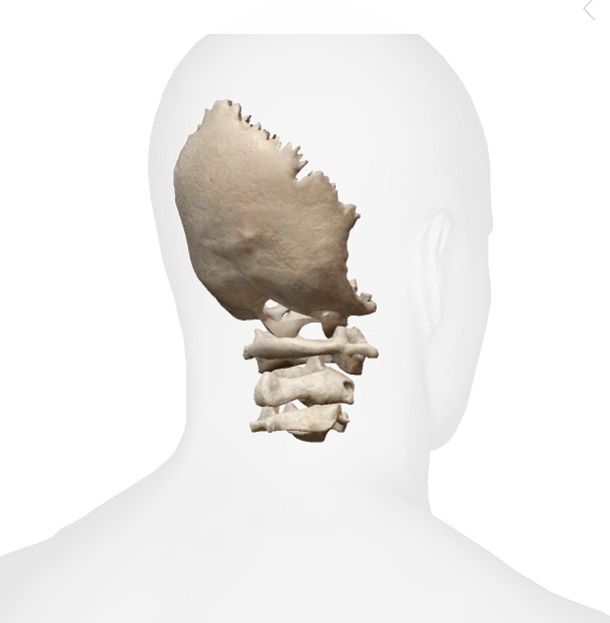

ΑΤΛΑΝΤΟ-ΙΝΙΑΚΗ ΕΝΩΣΗ (ΒΑΣΗ ΚΡΑΝΙΟΥ)

Σύμφωνα με τον Dr. Sutherland, το Σφηνοειδές και το Ινιακό οστό παίζουν ένα σημαντικό ρόλο στη κινητικότητα των οστών του κρανίου. Ενώνονται με την Σφηνοϊνιακή άρθρωση. Το Σφηνοειδές οστό είναι το κλειδί της κίνησης και το Ινιακό το ακολουθεί, κάτι που συμβαίνει και με τα υπόλοιπα οστά του κρανίου. Το ίδιο ισχύει και για το Ιερό οστό, το οποίο επηρεάζεται από τη κίνηση του Ινιακού μέσω του σπονδυλικού σωλήνα (dura tube).